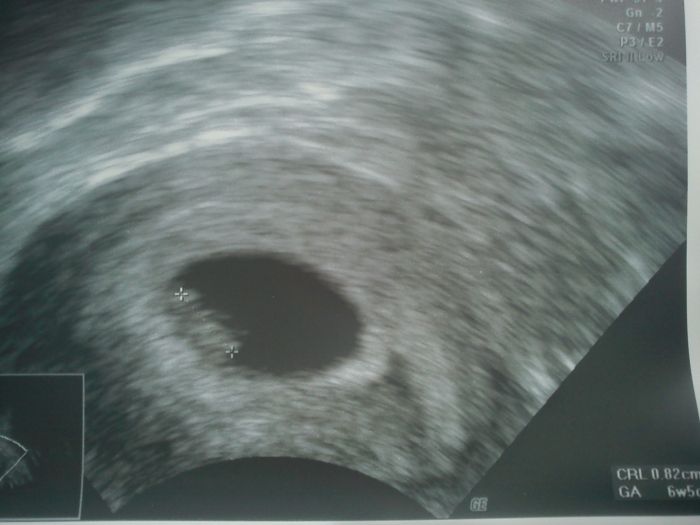

Teď jsem podle kalkulačky 8plus3 s termínem porodu 27.2... první kotrola za mnou, srdíčko tluče o stošest, vše zatím v pořádku - ani žádné těhu problémy zatím, takže ťuk,ťuk

Taky první ultrazvuk našeho gumídka